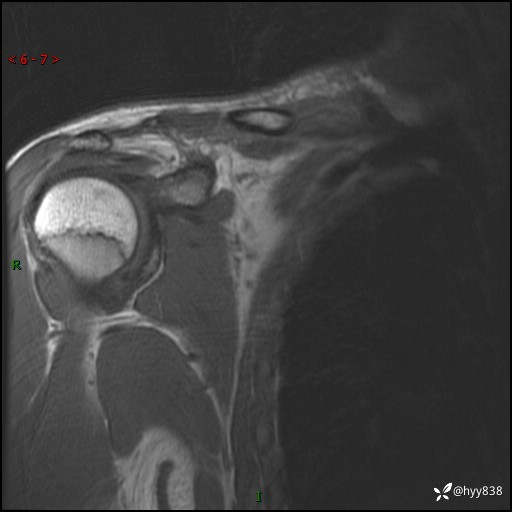

MRI(cor T1WI+T2WIfs+axi T2WIfs)